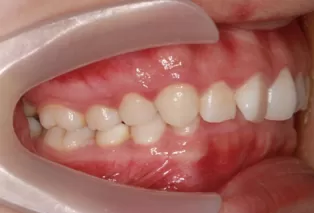

Photos intra-orales